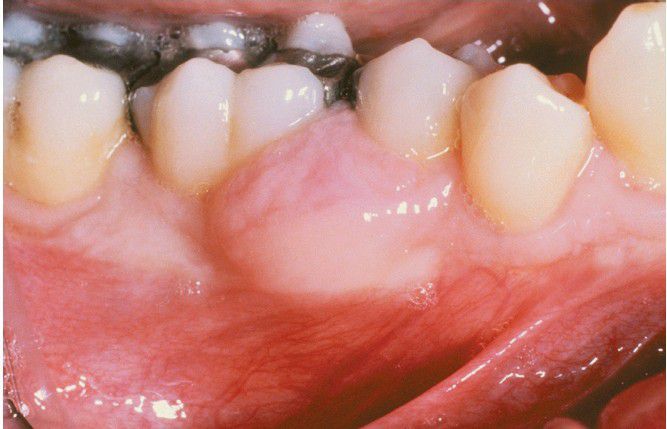

Peripheral Odontogenic Fibroma

This sessile gingival mass cannot be clinically distinguished from the common peripheral ossifying fibroma.